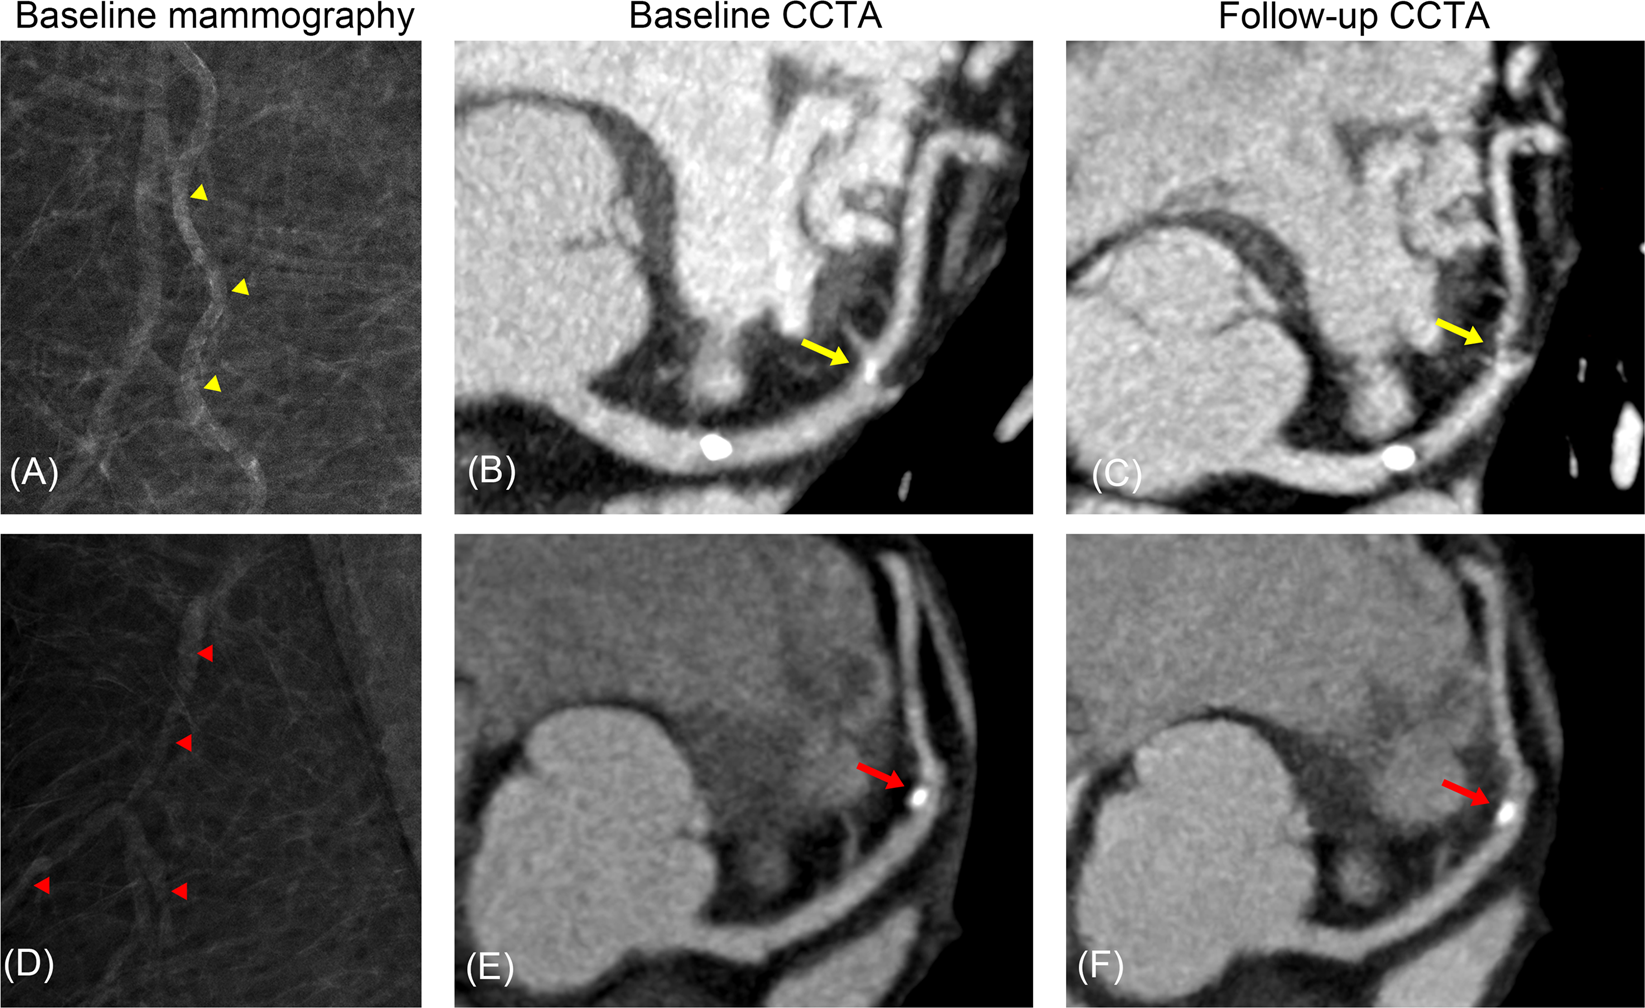

Figure 4

Representative cases. A 63-year-old asymptomatic woman with a BAC score of 5 (yellow arrow heads) on screening mammography (A) demonstrated calcified plaque without significant stenosis (percent diameter stenosis, 10–20%) at the proximal LAD and mixed plaque (percent diameter stenosis, 10–20%) at the mid LAD (yellow arrow). (B) Three years later, she was referred to the emergency department with chest pain and underwent CCTA, which demonstrated progression of the mid LAD lesion (percent diameter stenosis, 90%; yellow arrow). (C) Invasive angiography also demonstrated the tight stenosis of the mid LAD (percent diameter stenosis, 90%) and percutaneous coronary intervention was performed. A 51-year-old asymptomatic woman without evidence of BAC (red arrow heads) on screening mammography (D) demonstrated calcified plaque (percent diameter stenosis, 30%) at the mid LAD (red arrow). (E) Five years later, she visited the outpatient clinic due to epigastric pain and underwent CCTA, which demonstrated no change in the mid LAD lesion (red arrow). (F) BAC, breast arterial calcification; CCTA, coronary computed tomographic angiography; LAD, left anterior descending artery.